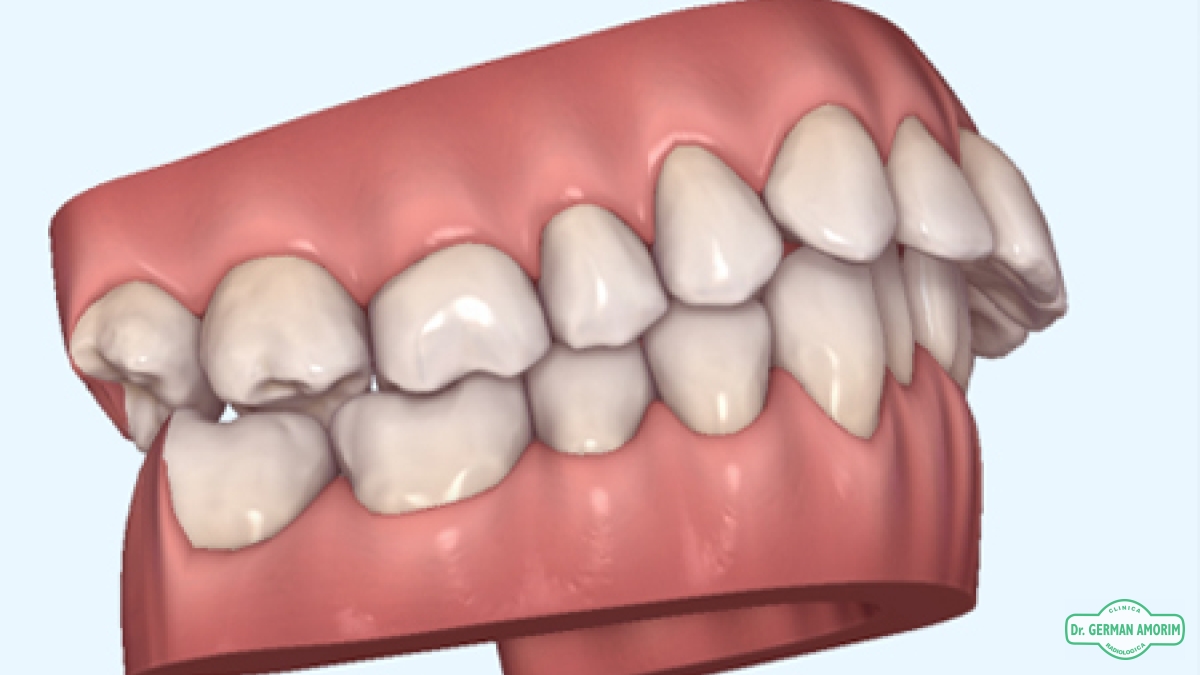

Cada paciente es único y por lo tanto lo son sus estructuras óseas,  la alineación de sus dientes, así como la oclusión, (su mordida)

• Fotografías digitales intraorales

• Modelos zocalados

• Modelos digitales

• Escaneo intraoral